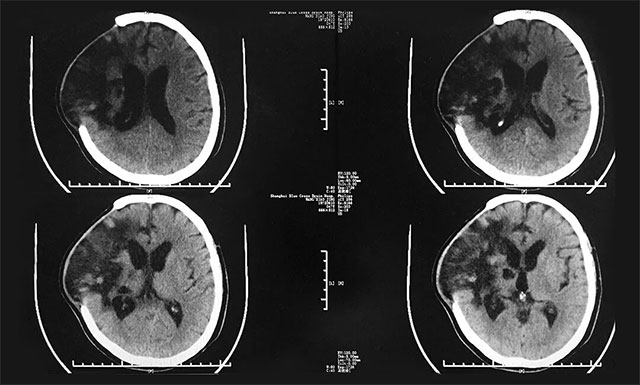

据患者丈夫回忆,去年12月14日,张女士在健身房做完运动后突发脑出血而昏迷不醒,之后被120送往上海某医院进行救治,并初步确诊为右侧额颞叶脑出血。因其脑出血量比较大,约为80毫升,于急诊先后进行了右颞脑内血肿清除术,颅内压监护探头置入术以及去骨瓣减压术,经过治疗,患者病情基本稳定,但仍处于昏迷状态,家人很是担心。现为求进一步治疗,患者慕名就诊于上海蓝十字脑科医院。

▲ 入院前,患者脑部感染严重

入院后,潘仁龙主任对患者进行了全面而细致的检查,并针对其之前脑出血的情况予以营养神经、改善微循环、促醒、抗感染、补液等对症治疗;同时,还邀请康复科专家、高压氧科专家及中医科专家分别进行会诊,并给予相应辅助治疗,之后患者情况较前有所好转,GCS评分也从之前5分变为8分(E4分、V1分、M3分)。